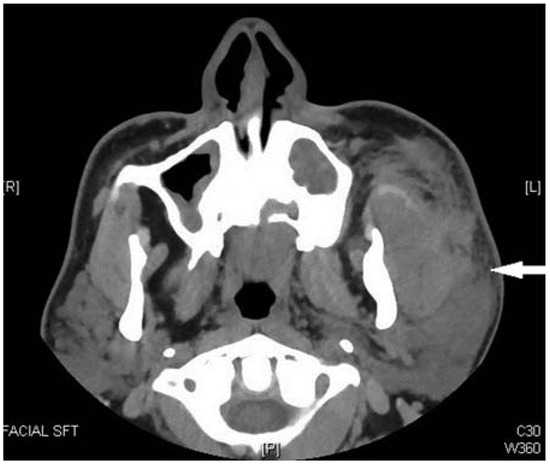

The patient was taken to the operating room and under-went open reduction and internal fixation of the left mandibular angle fracture utilizing a miniplate osteosynthesis via transoral approach (Figure 3). The patient’s immediate postoperative course was uneventful and he was discharged thenext day.

Figure 3. Postoperative orthopanorex showing fixation of the left angle fracture with a 2.0 Champy plate.